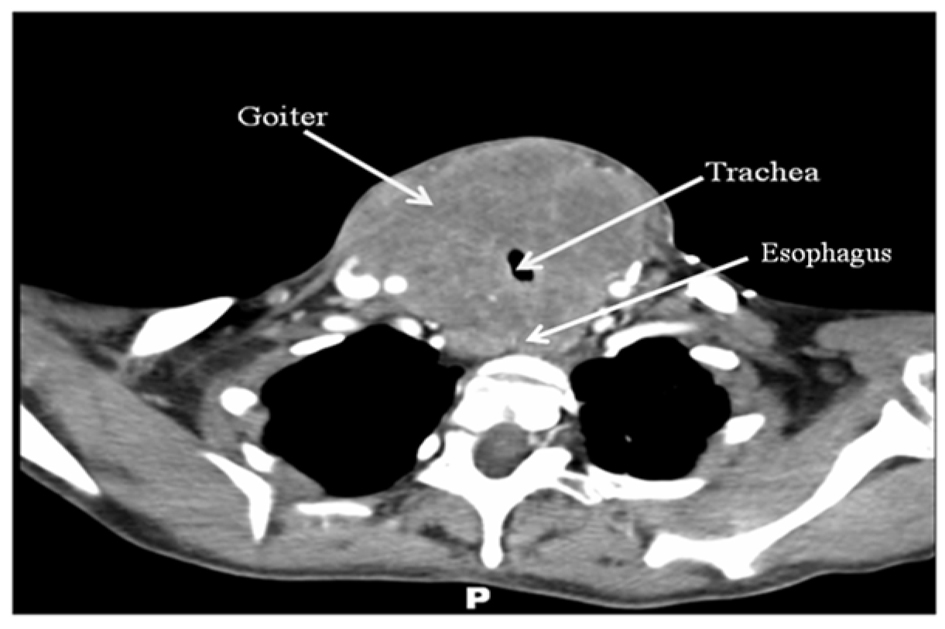

Computer tomography imaging with intravenous contrast (Fig. 1) was obtained and demonstrated a homogeneously enhancing solid mass, measuring 8 cm × 9 cm × 15 cm, arising from the thyroid gland with circumferential encroachment on the central airway narrowing the tracheal lumen to 6 mm at the level of the clavicles. No satellite lesions or lymphadenopathy was noted. No lytic or blastic bony lesions were seen.

![]() Click for large image | Figure 1. CT scan of the neck with intravenous contrast revealing a large mass originating from the thyroid gland with compression of surrounding structures. No obvious lymphadenopathy, satellite lesions, or bony lesions. |